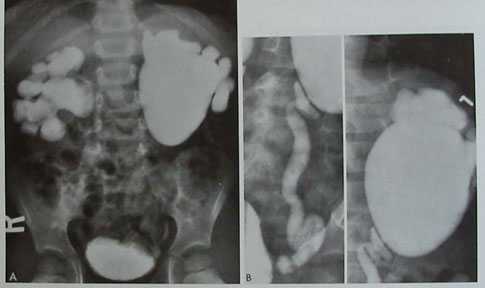

Урологическое обследование при обструкции пиелоуретрального сегмента (ПУС) должно включать и микционную цистоуретрографию для исключения пузырно-мочеточникового рефлюкса (ПМР). При ПМР высокой степени может возникать расширение почечной лоханки и перегиб пиелоуретрального сегмента. Незначительный пузырно-мочеточниковый рефлюкс иногда сопровождает классическую обструкцию ПУС. D.Ellis (1997) (Рис.5). Традиционная экскреторная урография по данным отечественной литературы остается в настоящее время основным методом подтверждения гидронефроза. Важным дополнением является катетеризация мочевого пузыря во время исследования у младенцев и полное опорожнение детрузора до обследования у старших детей. Однако нужно знать, что экскреторная урография дает только общие представления о функции почки. Цифровые же данные динамики функции почки можно получить только при нефросцинтиграфии.

Рис.5. А. Экскреторная урография выявила у мальчика 4-х лет с повторными болями в животе и подъемами температуры двусторонний гидронефроз.

В. Предоперационная микционная цистография установила двусторонний ПМР 4 ст. с обеих сторон. (SB Bauer,Campbell's Urology 1997)

На экскреторных урограммах в случае гидронефроза отмечается расширение лоханки и чашечек, мочеточник не контрастируется, либо определяется в дистальных отделах без признаков расширения диаметра. Максимальное увеличение размеров коллекторной системы почки наблюдается на поздних или отсроченных снимках (40 минута, 90 мин., 3часа.). Лазиксная проба на фоне экскреторной урографии используется для уточнения диагноза преимущественно у старших детей (Н.А.Лопаткин, А.Г.Пугачев (1984). Методика данного исследования заключается в следующем: ребенок предварительно обильно поится (гидратация), опорожняет мочевой пузырь. Первый исходный снимок выполняется на 15 мин. после введения контрастного вещества ( в стандартных возрастных дозировках). Далее внутривенно вводится лазикс из расчета (1мг/кг). Выполняются 3 снимка на 1мин.,5мин. и 10 мин. после введения лазикса. Признаками обструкции считают увеличение размеров лоханки и чашечек на 30% по сравнению с исходными размерами (15 мин.).